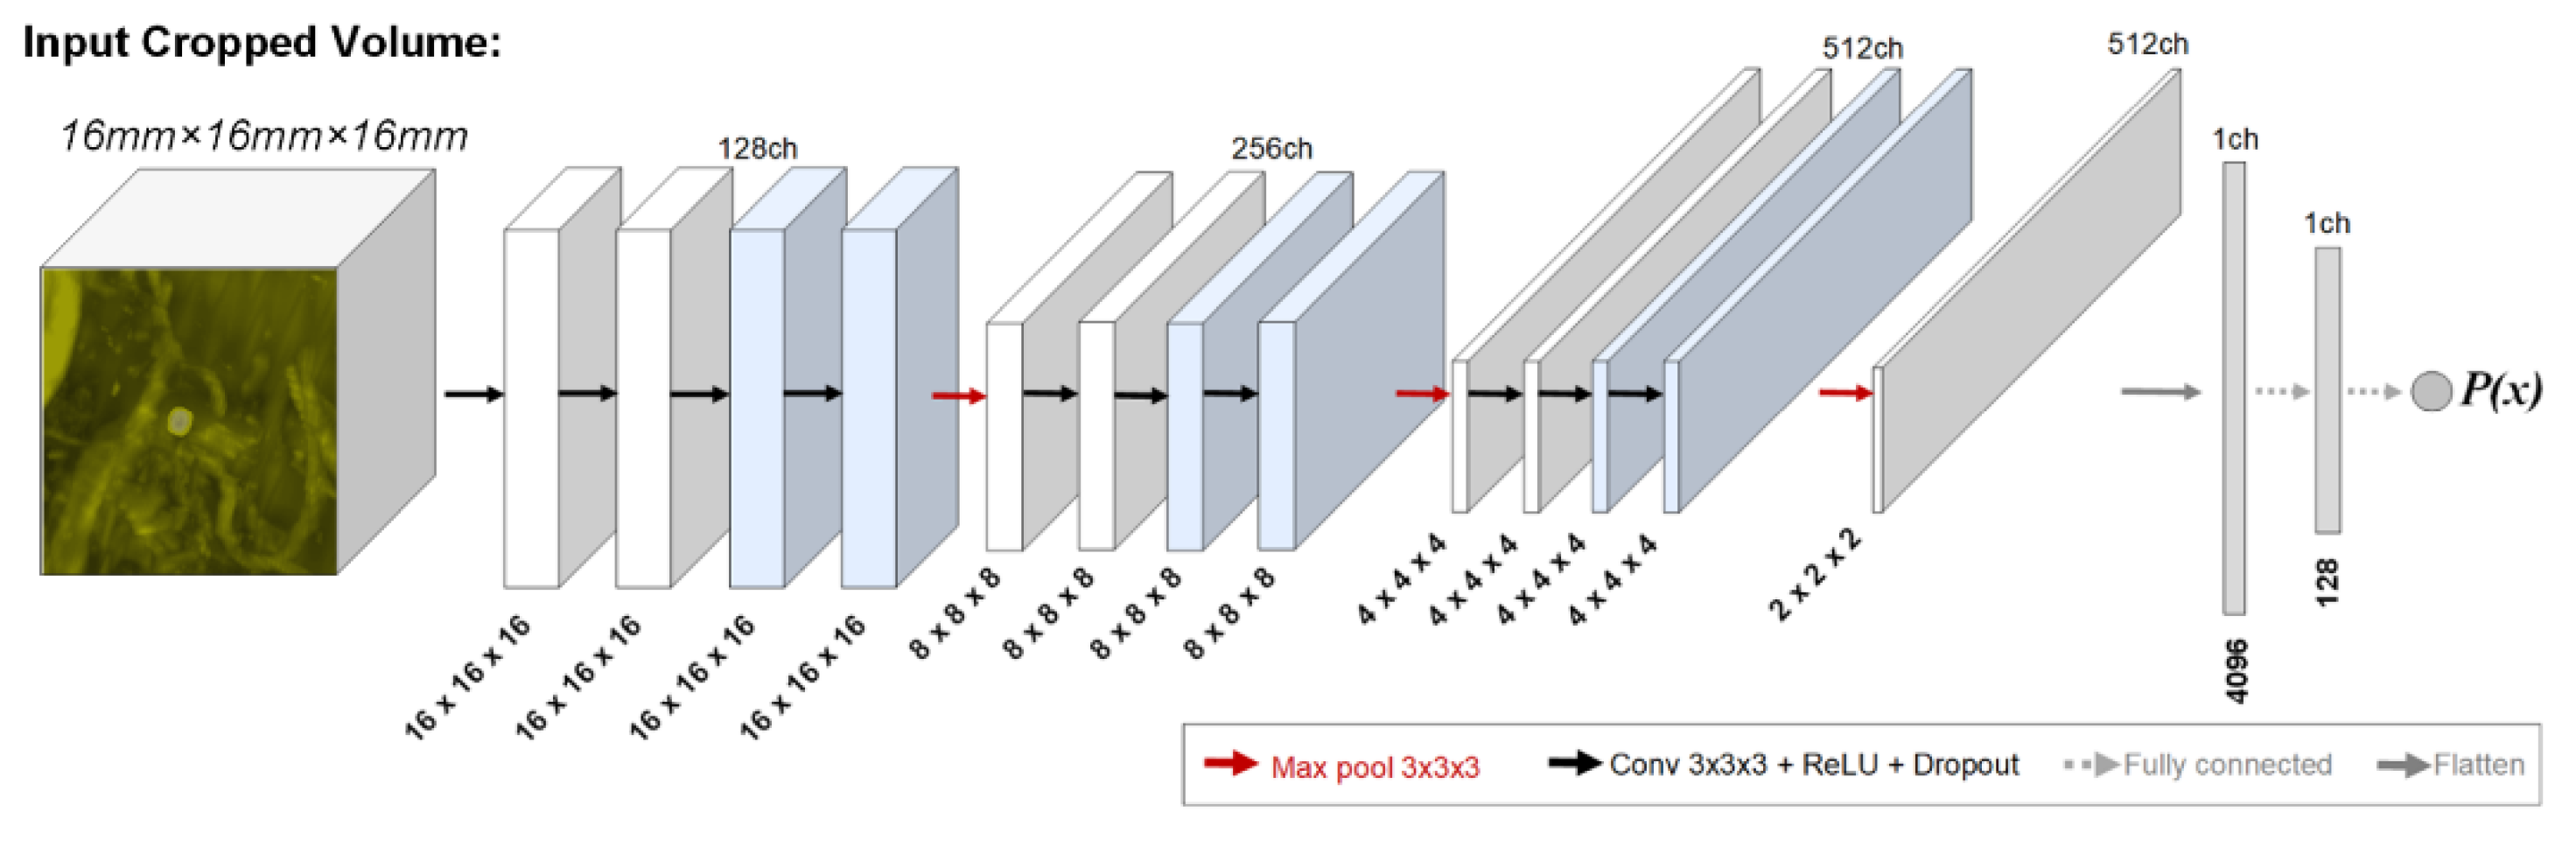

2.1. BM Detection Framework Overview

2.2. Teacher–Student Models and Noising Mechanisms